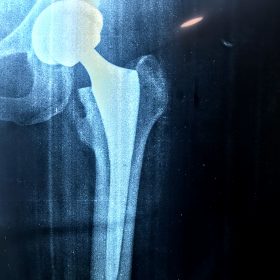

Παραδοσιακά οι αρθροπλαστικές ισχίου αποτελούνται από μια μεταλλική μπάλα – σφαίρα τοποθετημένη σε μια πλαστική κοιλότητα (κοτυλιαία πρόθεση).

Η πλαστική επιφάνεια στήριξης φθείρεται με την πάροδο του χρόνο, με ρυθμό μάλλον σχετιζόμενο με το επίπεδο δραστηριότητας του ατόμου. Αυτό έχει σαν επακόλουθο νεότεροι ασθενείς με μεγαλύτερο προσδόκιμο ζωής να έχουν αυξημένο ρίσκο αναγκαιότητας δεύτερης αρθροπλαστικής ισχίου (αναθεώρησης – Revision) επέμβαση που είναι πολυπλοκότερη και υπόκεινται σε υψηλότερο κίνδυνο επιπλοκών. Βάση των ανωτέρω, ιστορικά, η αρθροπλαστική ισχίου σπανίως εφαρμοζόταν σε ασθενείς κάτω των 60 ετών.

Χάρη στα νέα τεχνολογικά επιτεύγματα έχουν παραχθεί επιφάνειες στήριξης που ανταποκρίνονται σε μεγαλύτερα επίπεδα δραστηριότητας και αναμένεται να έχουν μεγαλύτερη διάρκεια ζωής. Αυτές οι καινούριες επιφάνειες στήριξης είναι συνήθως μέταλλο πάνω σε ειδικό σκληρότερο πλαστικό ή κεραμικό πάνω σε κεραμικό. Ως εκ τούτου, είναι τώρα πολύ πιο σύνηθες, νεότεροι ασθενείς να χειρουργούνται καθώς η πλειονότητα αυτών, που η αρθρίτιδα τους προκαλεί αφόρητους πόνους, επιλέγουν να έχουν ποιότητα ζωής από το να ζουν με τον πόνο.